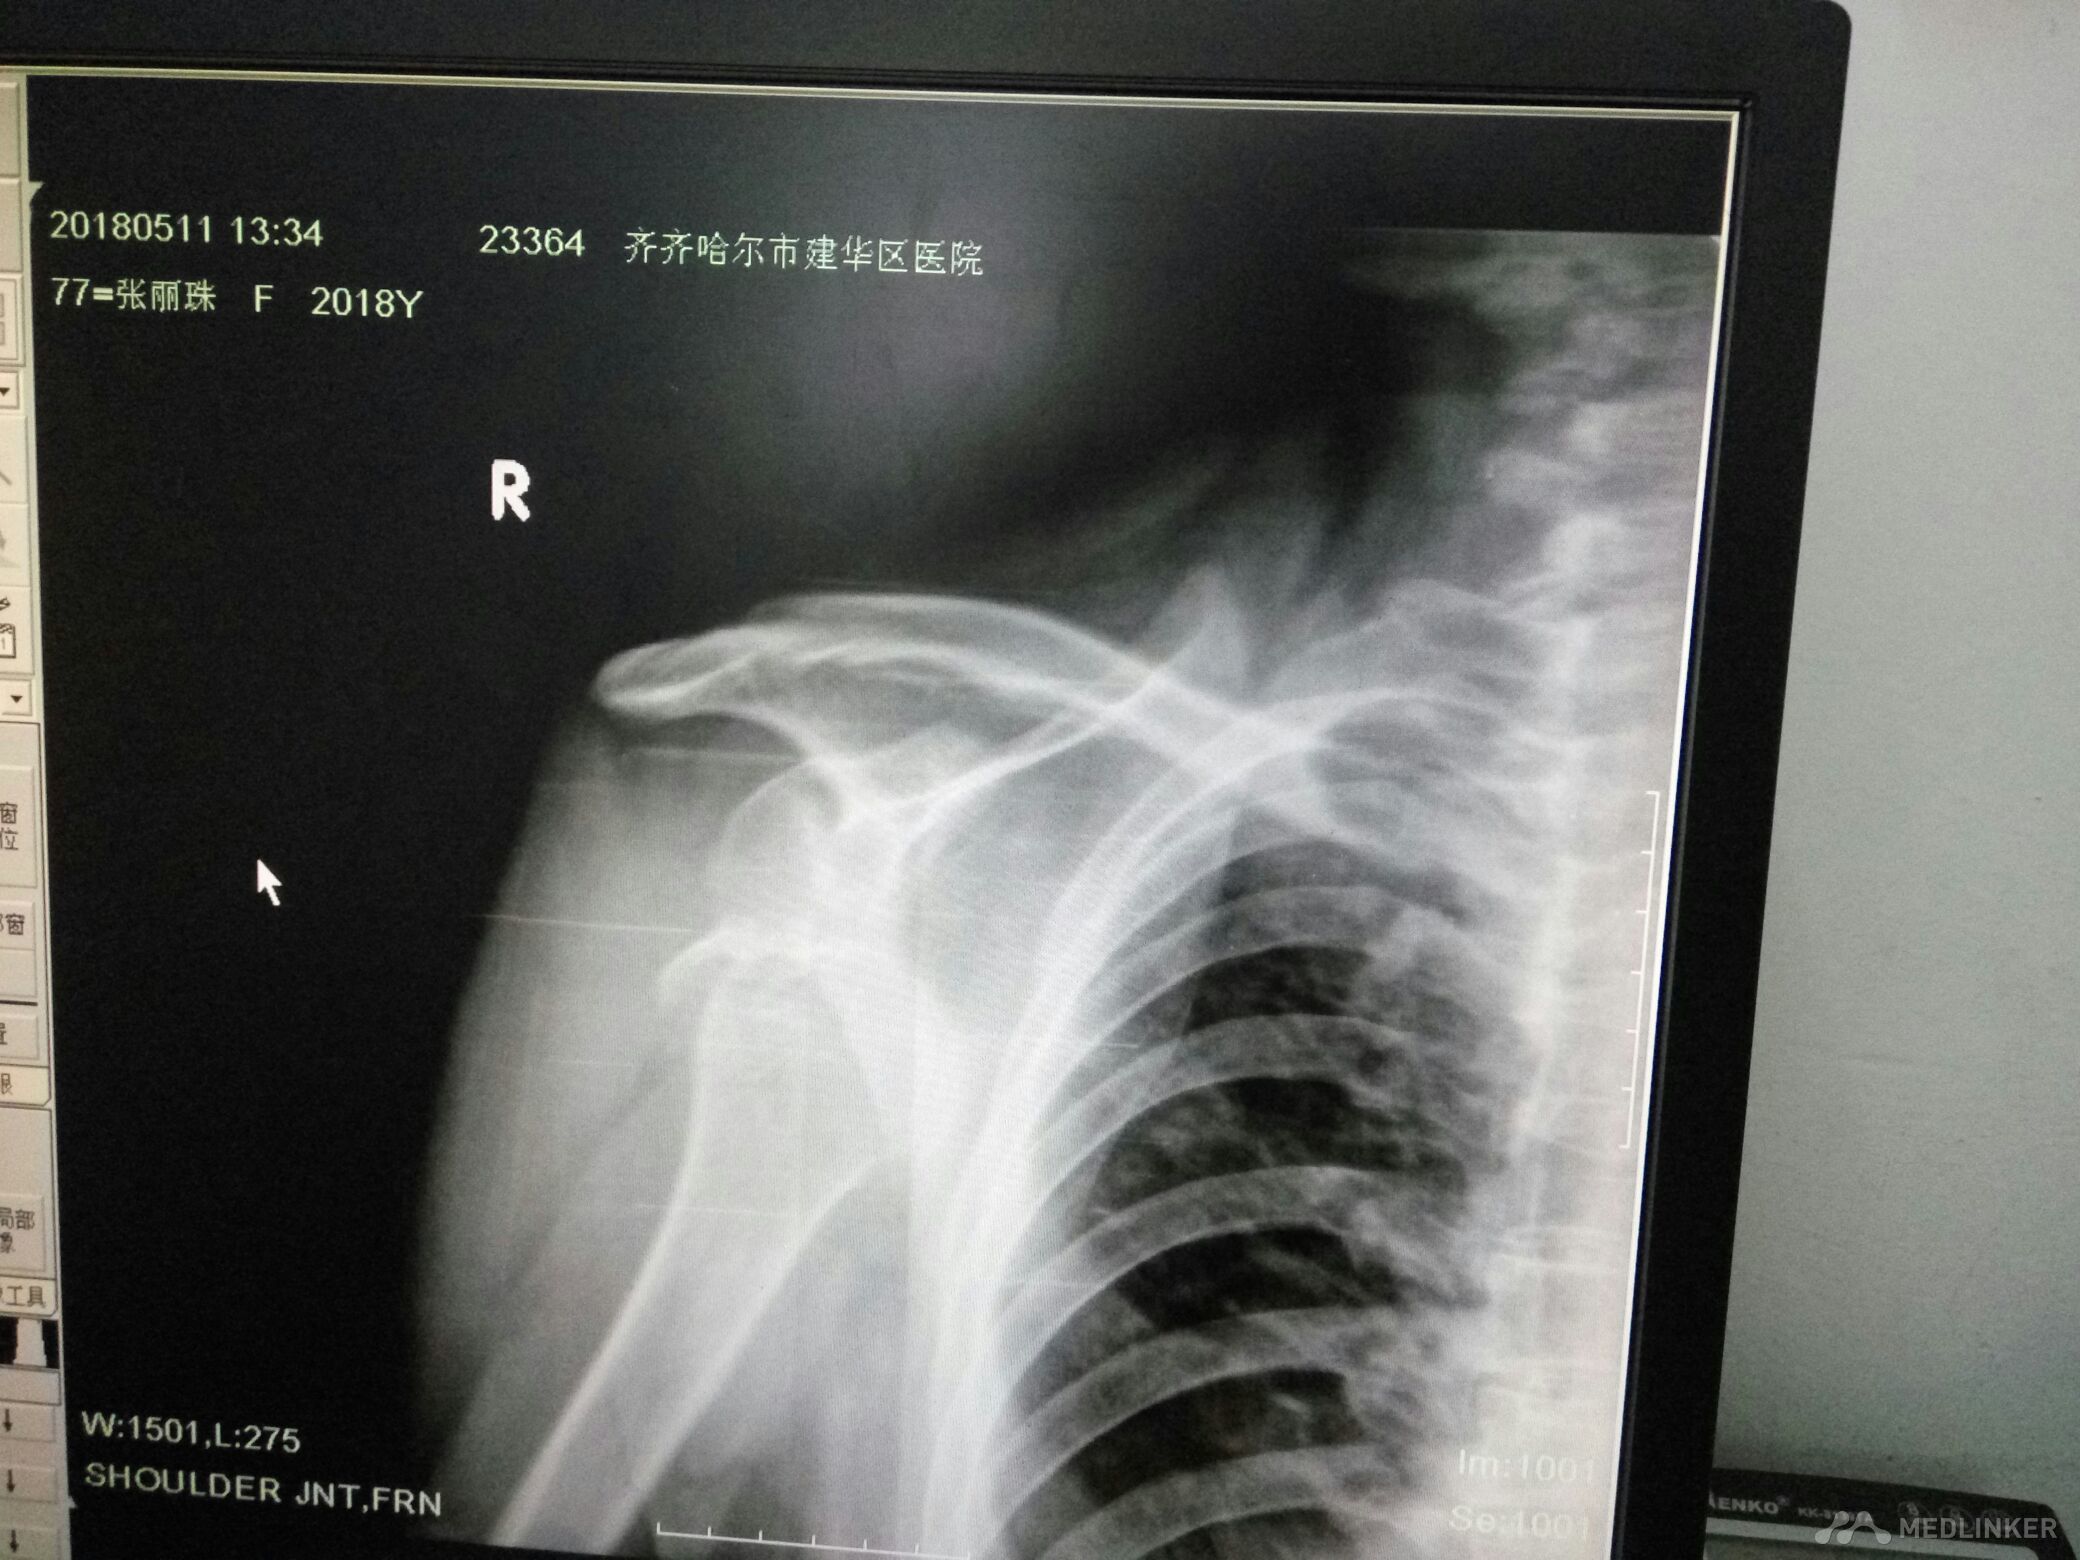

右肩关节脱位并肱大结节撕脱性骨折

该患者女77岁不慎跌倒所致肩关节活动丧失局部疼痛来齐齐哈尔市解放门医院骨科经张立群医生诊断肩关脱位拍片检查右肩关节脱位并肱骨大结节骨折经手法整复后拍片检查复位成功肱骨大结节骨折对位对线良好。